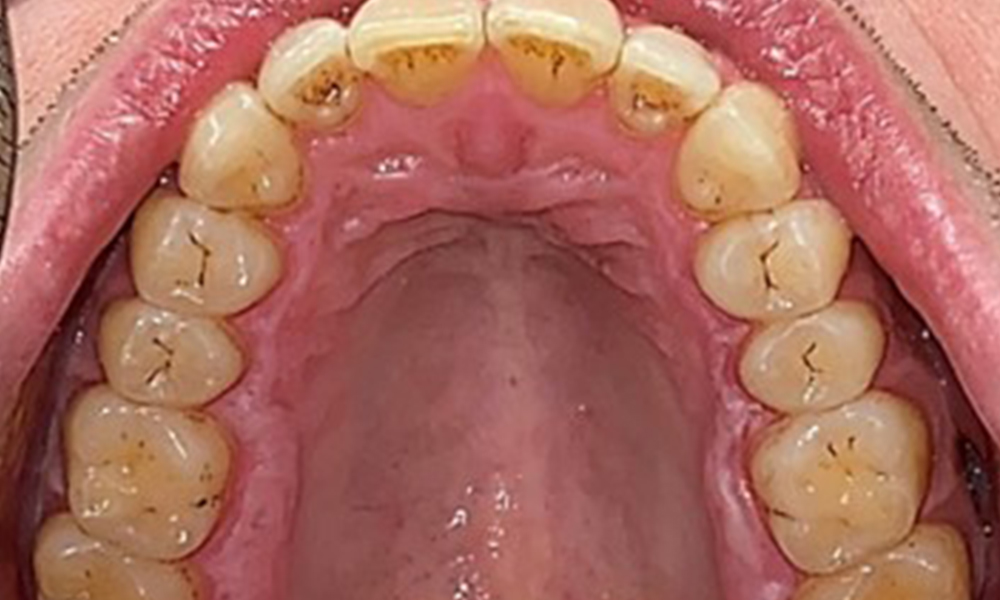

Occlusal view of the mandible.

Fig. 4: Occlusal view of the mandible, © Dr R. Krapf

The patient has full dentition with a total of 28 teeth. There were noteworthy erosions and attritions. (Fig. 4, Fig. 5). Due to bruxism, the patient has been wearing a splint with an adjusted bite block at night for many years. The erosions were caused by long-term consumption of isotonic beverages. No periodontal bone loss or active caries were observed.